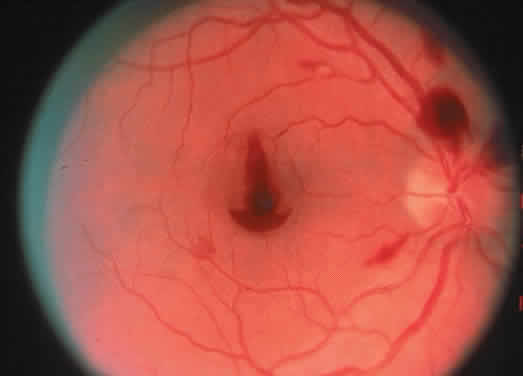

Protein S is a nonenzymatic cofactor necessary for the anticoagulant activity of activated protein C. Protein S by itself also has anticoagulant activity by forming a complex with C4b binding protein, a regulatory protein of the complement system. Protein S deficiency is inherited as an autosomal-dominant trait. Unlike protein C deficiency or antithrombin III deficiency, heterozygous protein S deficiency is not as strong a risk factor for thrombosis. Retinal artery occlusion has been described with protein S deficiency.25,29 Figure 2 shows a pregnant woman with protein S deficiency and a branch retinal artery occlusion (see Fig. 2).